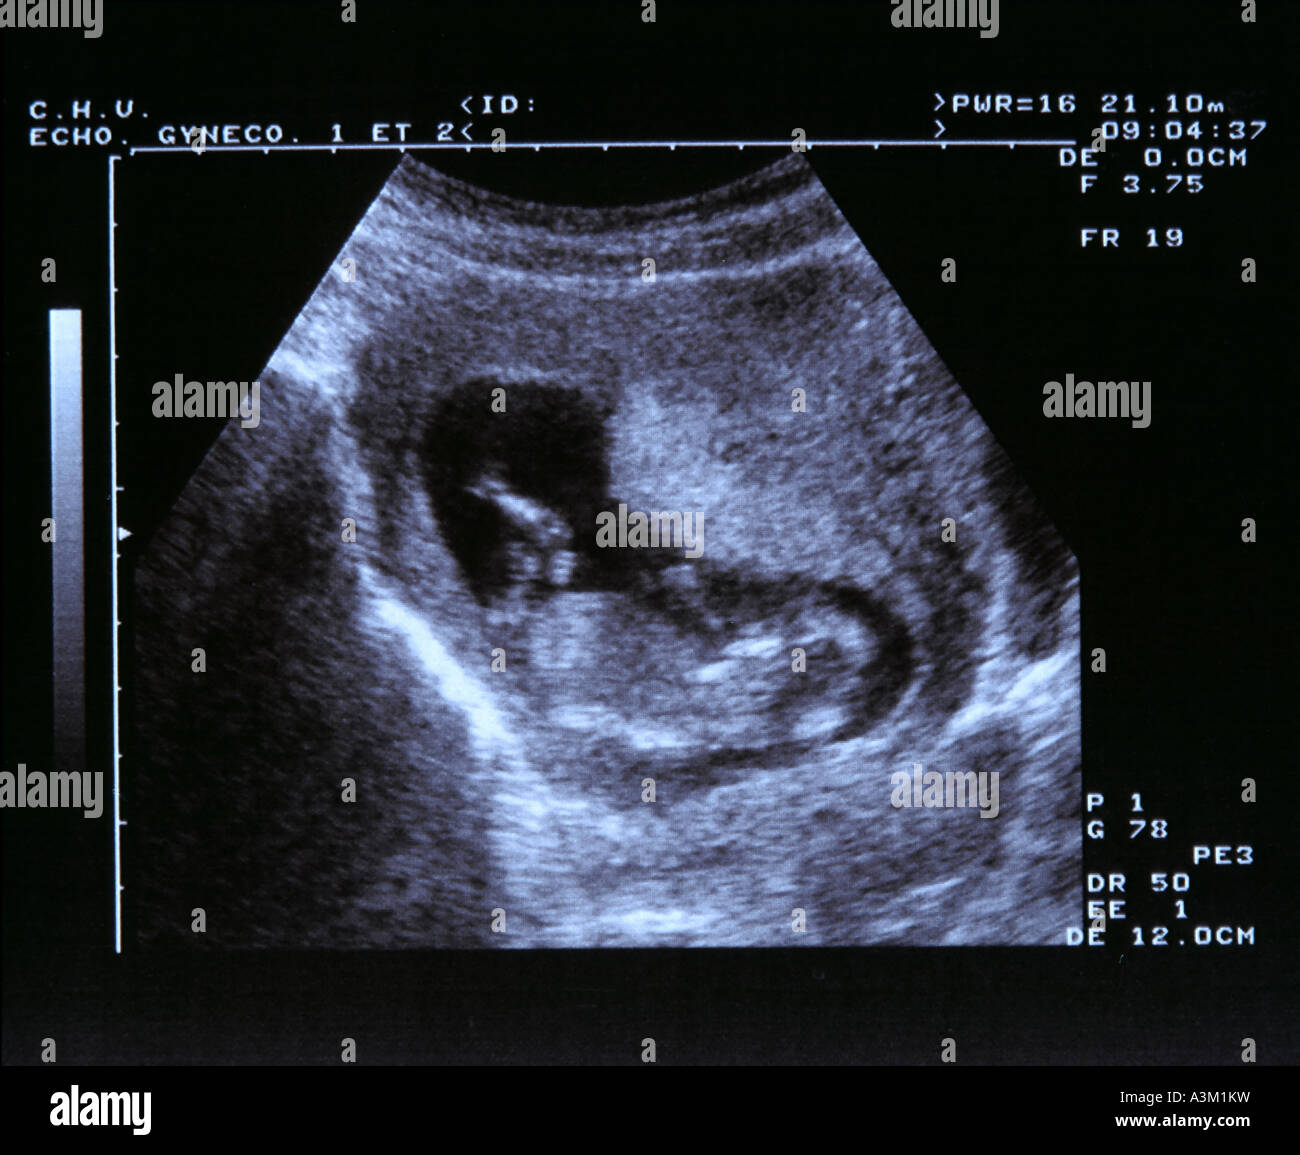

what does a 2 month old fetus look like

Posts: what does a 2 month old fetus look like